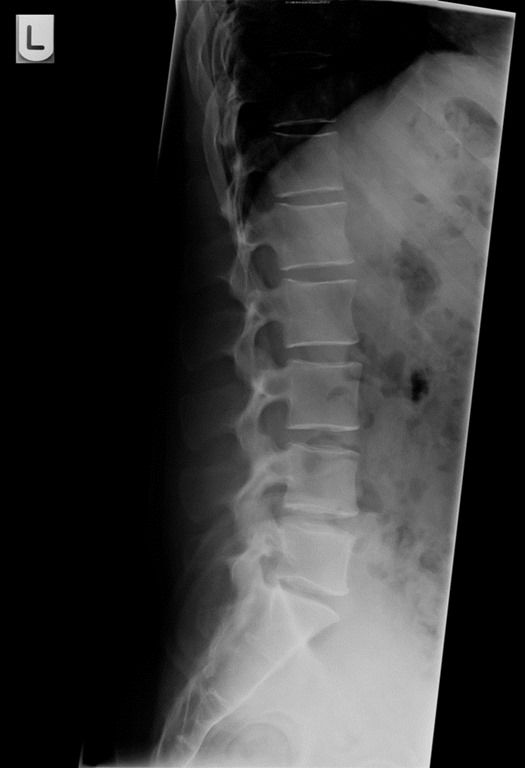

- I had been having some sciatic pain over the past year, and things just didn’t feel right. I had an xray to see what’s up. I thought it was a herniated disc (and I actually still do), but it’s being caused by an extreme curve that is pinching all my nerves there!

The left image is my lower spine. And the right image is what it’s supposed to look like. Yikes! Luckily physical therapy has been going well. I’m optimistic.